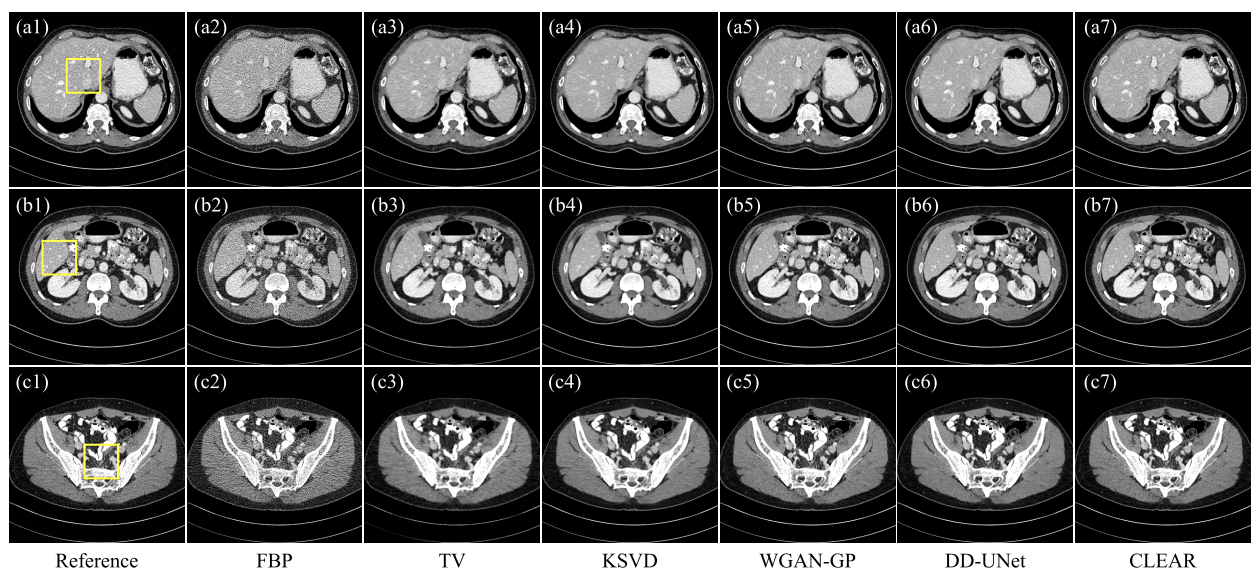

ablation study

- baseline : artifact (d2)

- CL 도입: artifact 억제, 과도한 부드러움 존재

- CLEAR:미세한 텍스처 보존, 시각적 인식 향상

정량적 평가

- 더 낮은 MAE와 PSNR

- 픽셀 단위의 손실을 최소화하도록 훈련-> MAE와 PSNR은 픽셀 단위 손실과 동일